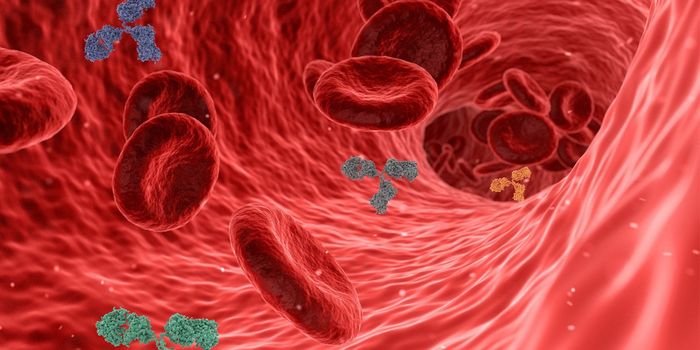

MAY 01, 2025ImmunologyVaccines generate a strong immune response designed to target a specific pathogen or disease. Many individuals think of ...

APR 15, 2025ImmunologyType 2 diabetes (T2D) is a complex and multifaceted disease that rarely exists in isolation. It is often entangled with ...

APR 14, 2025ImmunologyA study published in the British Medical Journal investigated the relationship between baseline low-density lipoprotein ...

APR 10, 2025ImmunologyLyme disease is a bacterial infection transmitted by tick bites. It often causes rash, fever, headaches, fatigue, and ot ...

MAR 19, 2025ImmunologyMaintaining cognitive health as we age is a growing concern, with researchers continuously exploring factors that influe ...

FEB 19, 2025ImmunologyMicronutrient deficiencies are a growing concern among individuals with type 2 diabetes mellitus (T2D), given their pote ...

JAN 28, 2025ImmunologyOzempic being a household name, GLP-1 receptor agonists (GLP-1RAs), a class of medications have garnered significant att ...

DEC 26, 2024ImmunologyCrohn’s disease is a type of inflammatory bowl disease (IBD) that can take place anywhere in the digestive tract. ...

DEC 12, 2024ImmunologyVaccines have advanced the field of health and medicine throughout the last century. They are commonly given before a di ...

DEC 05, 2024ImmunologyTreatment for solid tumors has improved in the last two decades with the emergence of immunotherapy. Immunotherapy is a ...

NOV 28, 2024ImmunologyCancer is a disease in which mutated cells grow rapidly and uncontrollably. Unfortunately, these cells resist the body&r ...